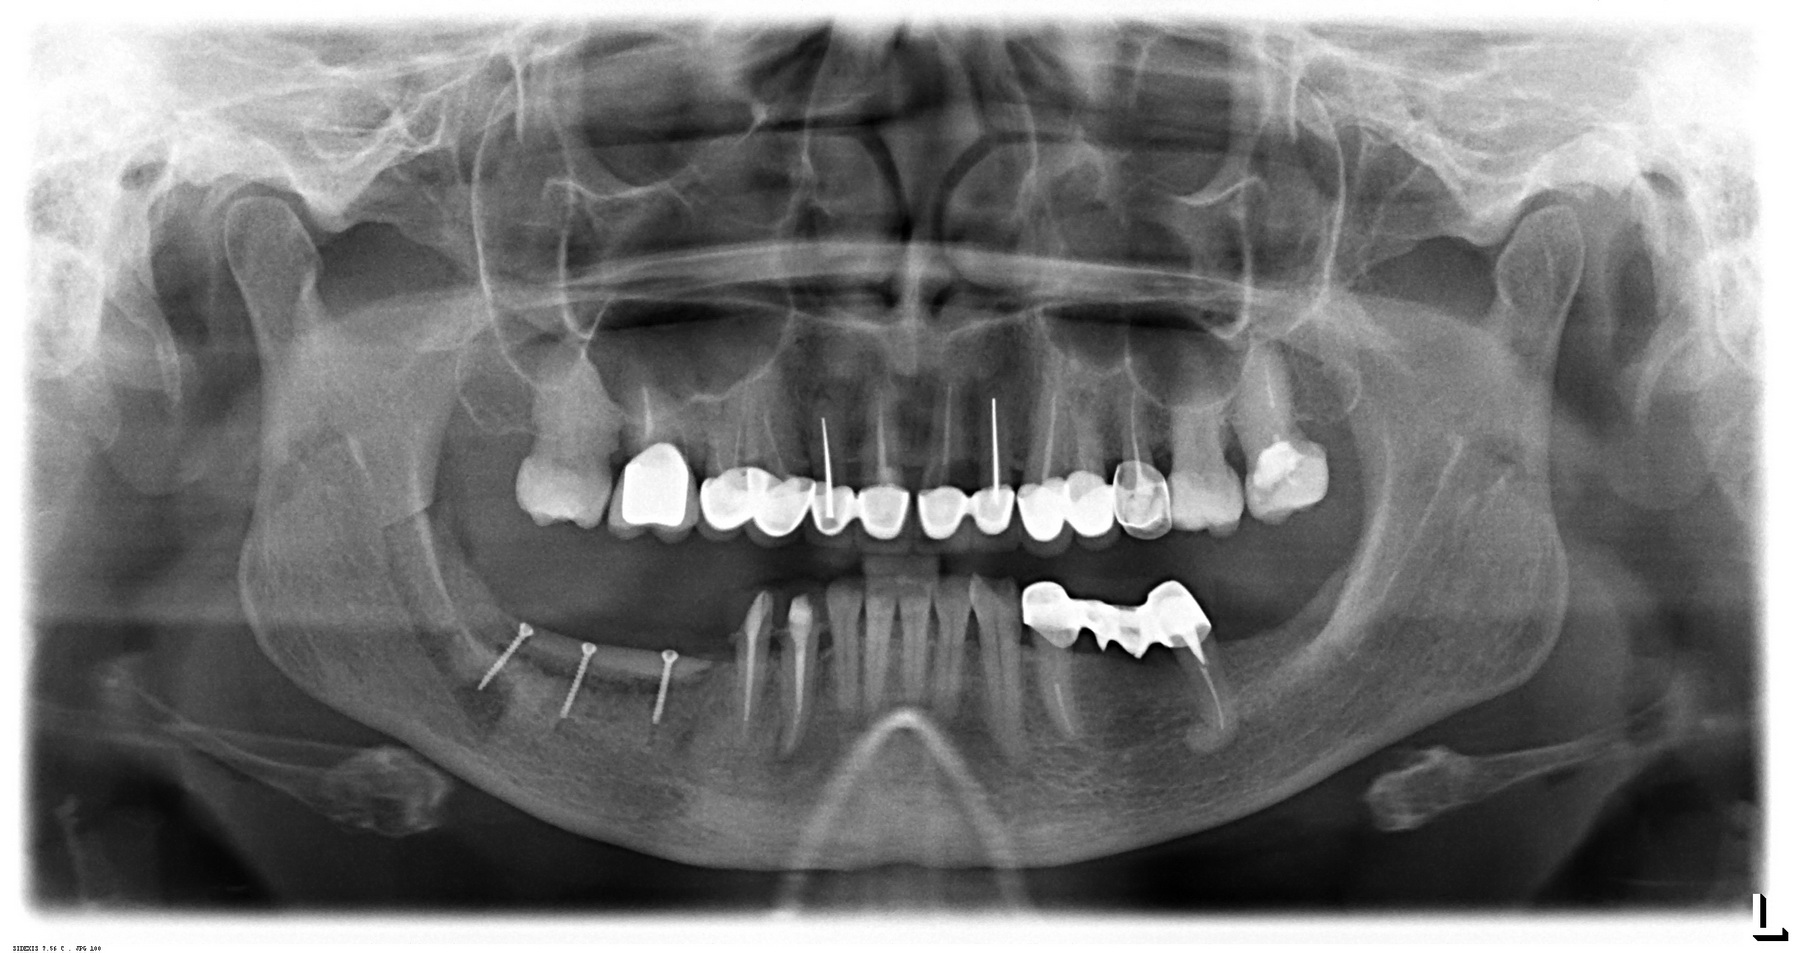

Пациентка, чей послеоперационный панорамный снимок вы видите в начале статьи, прошла несколько врачей, предлагавших ей разные способы лечения: от более-менее «возьмем мембрану, насыпем костный порошок» до хардкорных («подвздошная кость или свод черепа»). После обследования мы решили выбрать «золотую середину» — сочетать остеопластику аутотрансплантацией костных фрагментов с использованием барьерных мембран, биоматериалов и аутокостной стружки.

Контрольный снимок:

По нему, в принципе, видно, что было, что мы сделали и что получилось.